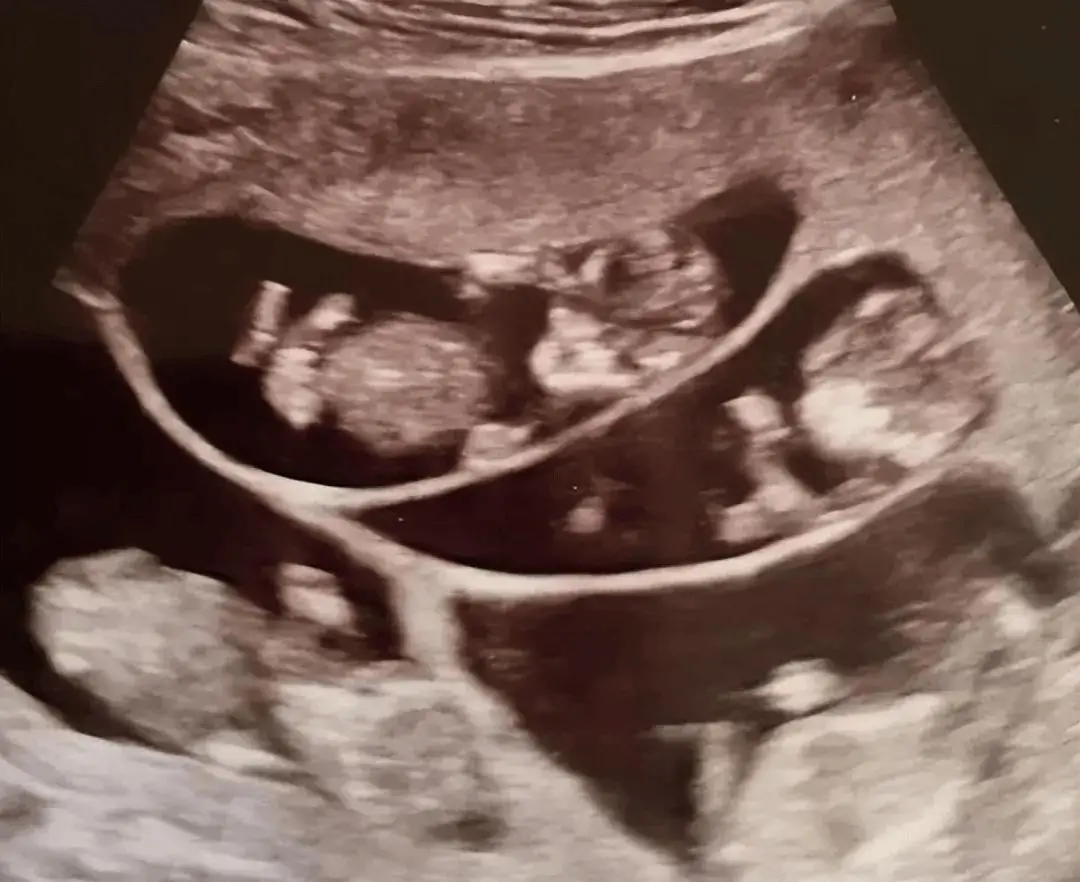

Bà mẹ trẻ mang bầu đa thai sau thời gian tìm con bằng thủ thuật hỗ trợ sinh sản.

Thông tin gây sốc khiến cả gia đình vừa vui mừng vừa lo lắng. Sức khỏe Bobbi vốn yếu, việc mang 7 thai đồng nghĩa với rủi ro rất lớn. Các bác sĩ khuyên nên “giảm thai chọn lọc” để bảo vệ mẹ và một số bé. Nhưng tình mẫu tử trỗi dậy mạnh mẽ, Bobbi kiên quyết giữ lại cả 7 sinh linh.

Kể từ khi biết mình mang thai bảy, Bobbi được đội ngũ y tế theo dõi đặc biệt. Để nuôi đủ 7 bào thai, bà buộc phải nạp tới 4.000 calo mỗi ngày, gần như cứ 40 phút lại ăn một lần. Thế nhưng, những cơn ốm nghén dữ dội khiến bà buồn nôn với hầu hết các món ăn, chỉ có thể trông cậy vào vitamin và khoáng chất bổ sung.

Đến tháng thứ năm, sức khỏe Bobbi tụt dốc. Bà gần như phải nằm liệt giường, từng cử động nhỏ cũng trở nên khó khăn. Vậy mà, suốt những ngày gian nan ấy, trong lòng Bobbi chỉ có một niềm tin rằng phải giữ cho tất cả con được chào đời.